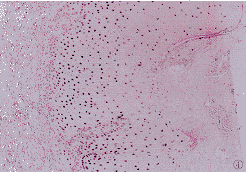

14例。80.33%(5/6)增生期KA即有凋亡现象,平均凋亡指数(43.33%)低于成熟KA(67.64%),但无显著性意义(P>0.05)。凋亡细胞在KA紧邻角栓的肿瘤区呈巢状分布,多数为圆形或椭圆形深紫蓝色团块(图4,5)。

图4 凋亡细胞在KA紧邻角栓的肿瘤区呈巢状分布.TUNEL×150

图5 凋亡细胞为圆形或椭圆形深紫蓝色团块.TUNEL×500

KA是好发于中老年皮肤暴露部位的丘疹、斑块或结节,中心可见火山口样角栓。常在2~3月内迅速生长,多数皮损1年内自然消退。男性好发。本组病人均发生在受日光照射的头面部,男女之比为7∶3。KA病因不明,众多学者对其自然消退的生物学进行了研究。Stephenson等〔3〕观察到炎性KA真皮组织有更多的Langerhan细胞浸润,因而认为与Langerhan细胞有关。Kerschmann等〔4〕通过与鳞状细胞癌p53表达和增殖指数比较,认为KA的自然消退与凋亡有关。细胞凋亡是一种受遗传控制的单个细胞主动自杀过程,是机体维持稳态的基础,也是肿瘤性疾病发生发展的重要因素。恶性度高、预后差的恶性黑素瘤凋亡细胞明显低于恶性度低、进展慢的基底细胞癌。肿瘤放疗、化疗后的疗效也与凋亡细胞的增加显著相关〔5〕。KA发展到一定时期即停止,罕见转移,属良性肿瘤性增生。本研究采用TUNEL法直接观察KA瘤细胞凋亡的形态学特征,发现80%KA(16/20)有细胞凋亡现象,70%(14/20)呈强阳性反应,表明凋亡为KA典型生物学特征。凋亡细胞分布于肿块中心的瘤细胞,多数为核固缩呈圆形或椭圆形深紫蓝色团块;少数细胞核染色质沿核膜形成环状,核质内有空泡形成。表明KA是从肿块的中心开始凋亡。5例增生期KA即有凋亡现象,但平均凋亡指数低于成熟期KA,提示从KA早期,增生和凋亡即同时存在,在KA的成熟期,增生逐渐降低,凋亡占优势,最终导致KA的自然消退。